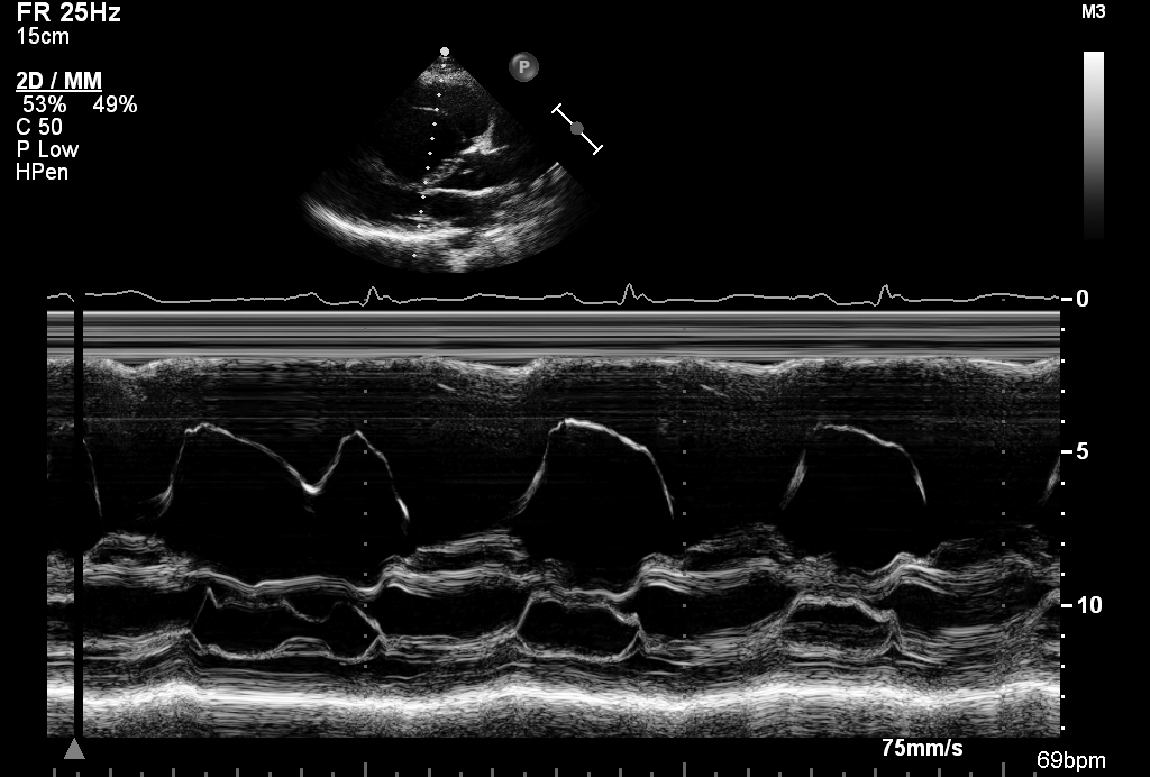

A 30-year-old woman who is normally fit and well presents with palpitations. Here ECG reveals an accessory pathway. Her ECG is shown in Fig 6.1, 6.2 and 6.3 and Videos 6.1, 6.2, 6.3, 6.4, 6.5,6.6, 6.7, 6.8, 6.9 and 6.10.